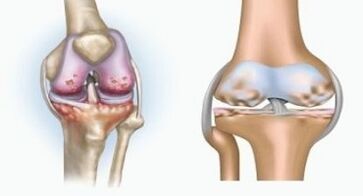

Arthritis is an inflammation of connective tissue, a synovial membrane that contains many vessels and provides lymphatic flow.The inflammatory process leads to a violation of the nutrition of joint tissues, as a result of which the production of joint lubrication - synovial fluid is limited.

Arthrosis is a degenerative-divophical process associated with the destruction of the articulation cartilage tissue.The cartilage is gradually destroyed, dry, the distance between the bones of the joint decreases, which is the cause of pain.In severe shapes, destruction affects bones.They become more porous, they lose their density, they become fragile.

For example, what is the difference between arthritis and osteoarthritis of the knee joint?With arthritis, the synovial layer of joint tissues occurs.This causes an increase in joint temperature.

The articulation increases, a persistent pain syndrome is developed, which intensifies during movement.With osteoarthritis, pain occurs only after physical activity, you can listen to a characteristic crunch or clicks in the joint, gradually the joint is deformed and loses mobility.

The difference between arthritis and osteoarthritis of the fingers and the hands of the hands is that the first disease is cured and the second does not.With arthritis, the synovial housing and the articulation capsule are touched.

The defeat of the cartilage and bone tissue occurs only in the last stages in a careless state.With osteoarthritis, the cartilage tissue is affected first, and then the bone, the inflammation of the synovial membrane is of secondary origin, that is, it develops against its background.